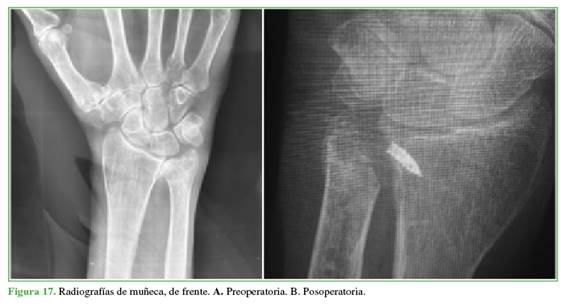

En la Figura 16, se muestran las radiografías pre y posoperatorias de un paciente y, en la Figura 17, imágenes pre y posoperatorias de otro caso de la serie.